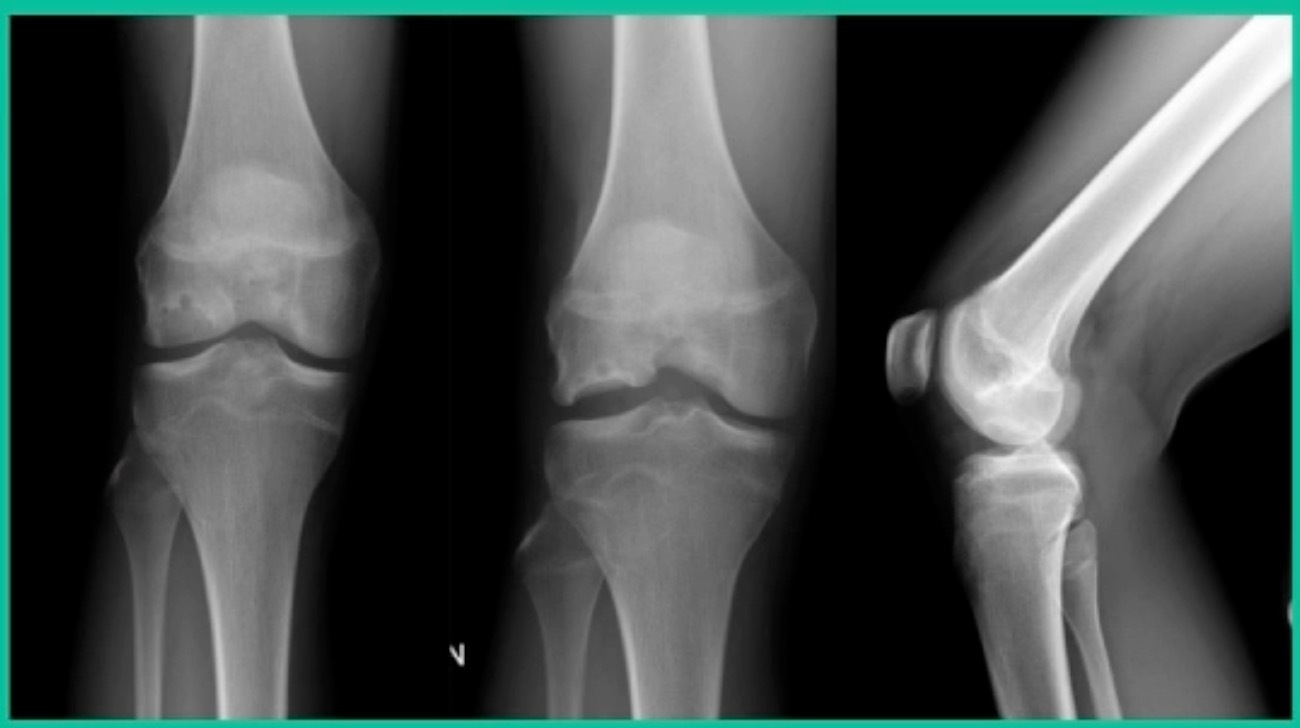

Now a couple of quick cases. This is juvenile OCD. This is the first series of three or four, just juveniles. 14-year-old, intermittent knee pain, lateral femoral condyle OCD (Figure 1).

This is an 11-year-old. Left knee lateral knee pain. Effusions, the same type of classic findings (Figure 3)

This is another one. 17-year-old basketball player (Figure 5).

Another case example. 14-year-old male tennis player, 10 months of knee pain (Figure 7A).

Now, we’ll shift to the adult. This is a 27-year-old. Right knee swelling, activity-related, and classic failed nonsurgical treatment on the lateral side of the knee.

This is an 18-year-old with a lateral femoral condyle OCD: